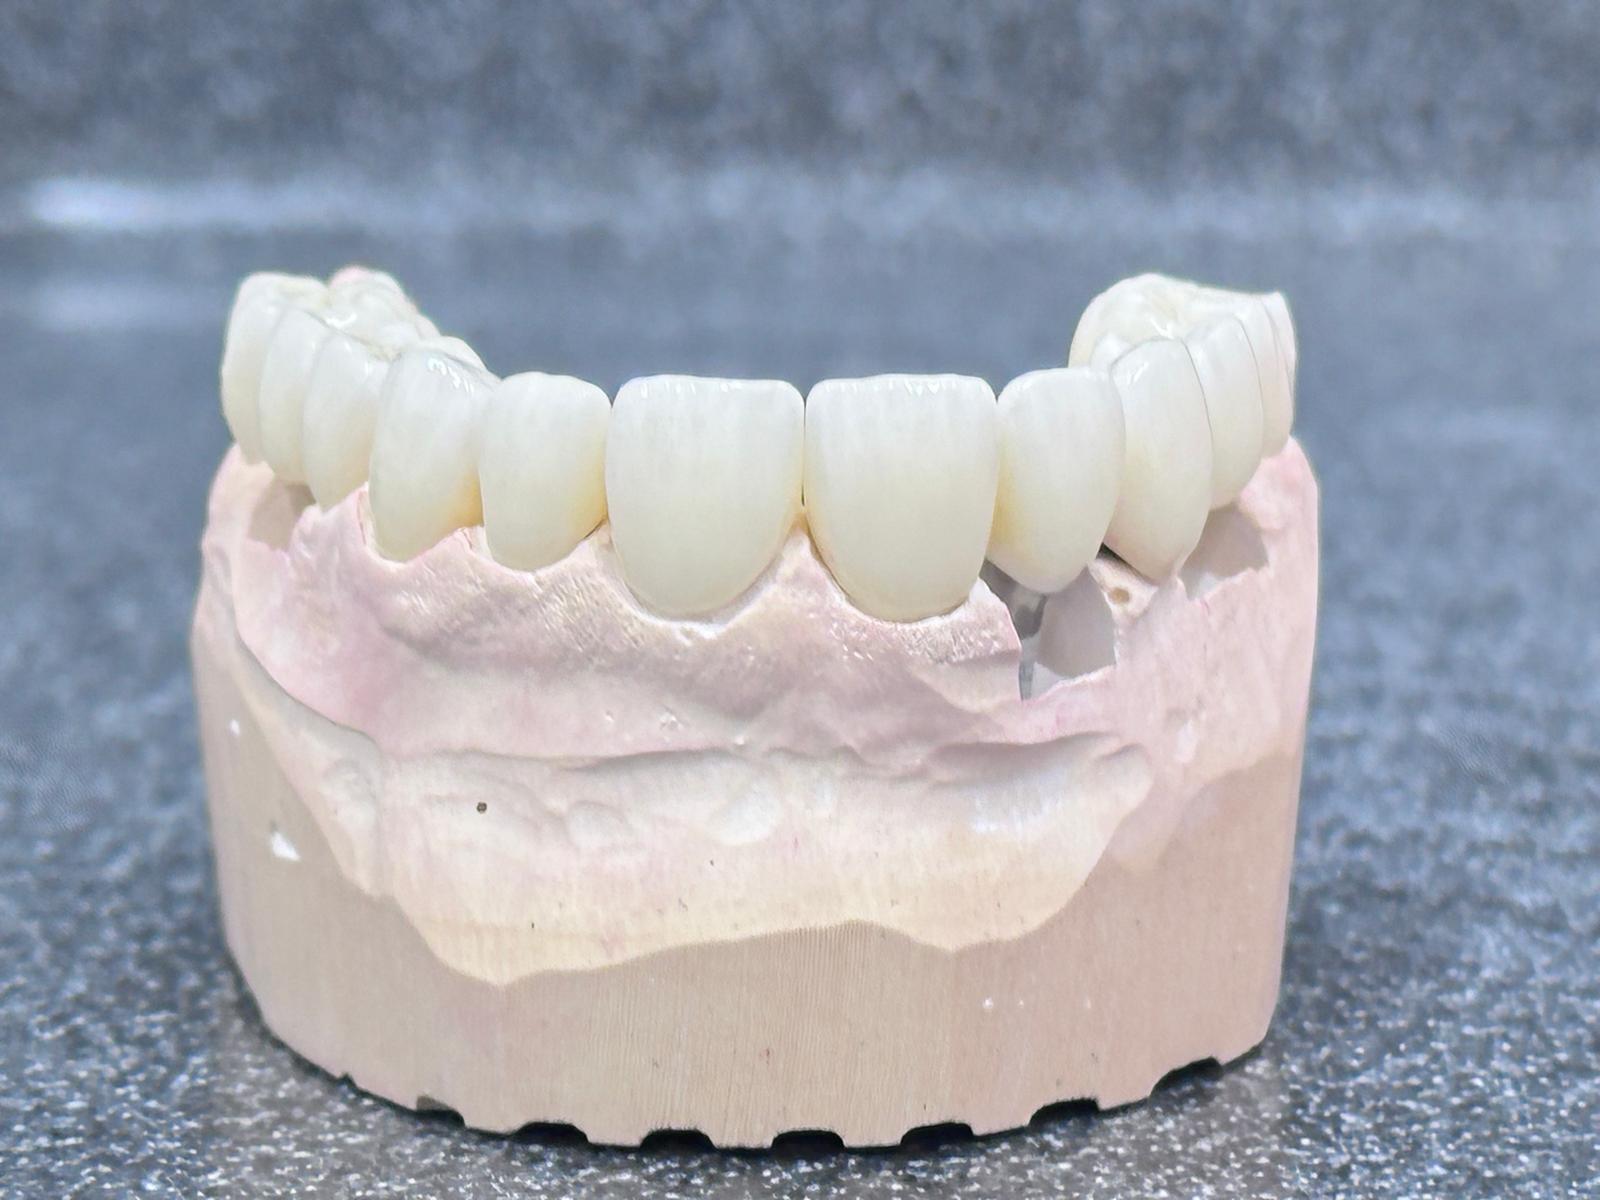

Implants placed using a digitally planned stackable surgical guide following alveolectomy, ensuring ideal positioning and a stable foundation for full-arch restoration.